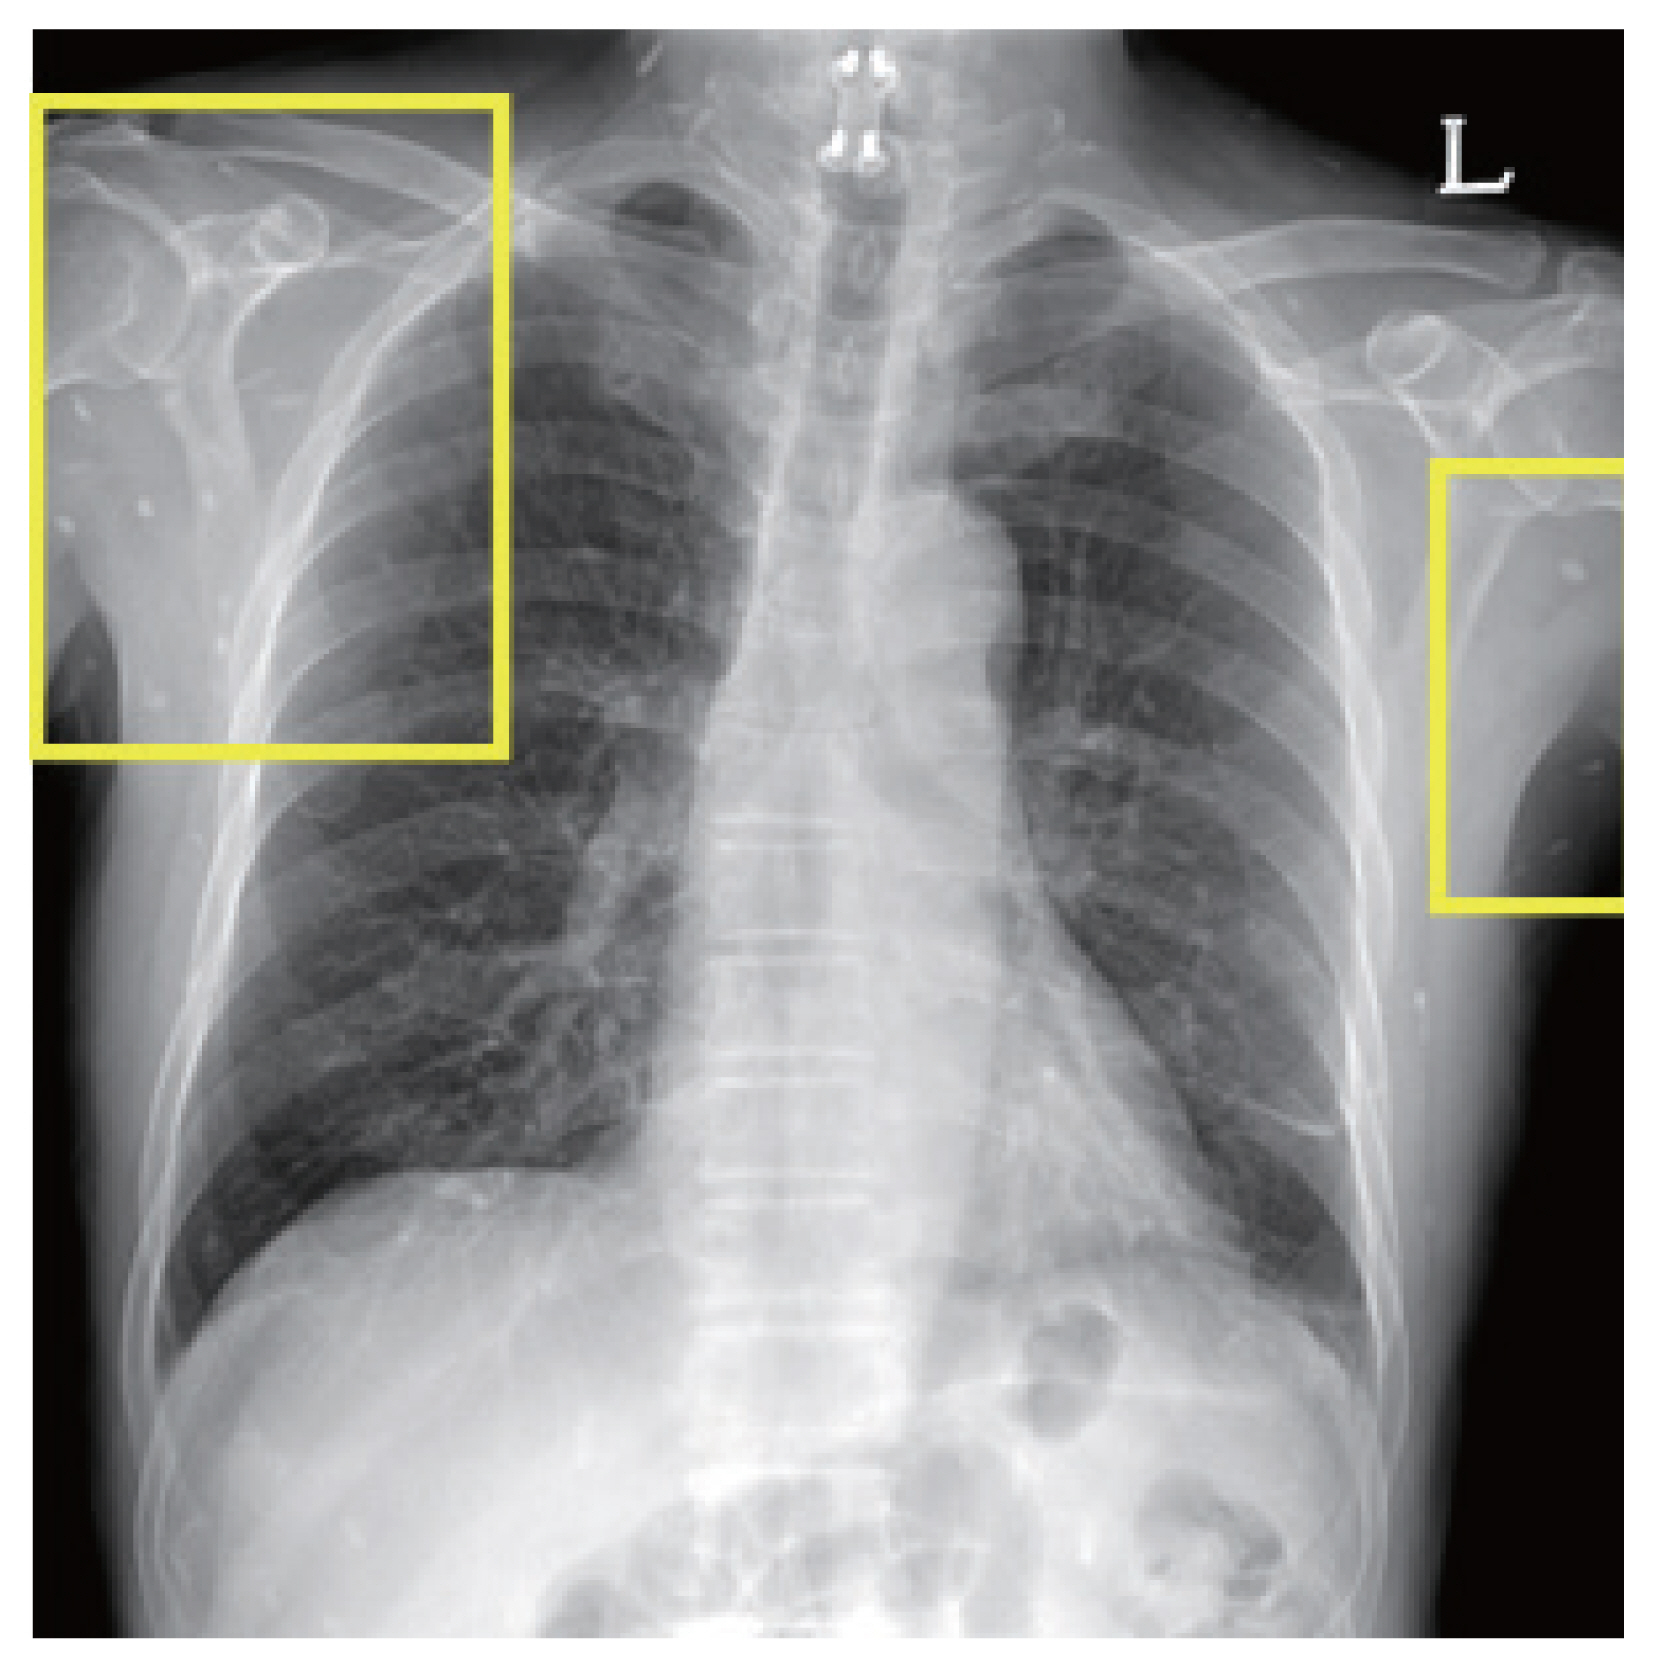

One of the patients was a 66 year old male with no previous medical history, who was admitted with symptoms of headache, vertigo, and gait disturbance. He had a history of working in Libya 35 years ago, and a history of travel to Vietnam (4 years ago) and China (1 year ago). CSF findings showed eosinophilic pleocytosis (CSF white blood cell count 29/μl, eosinophil percentage 18%), with elevated protein levels (89.3 mg/dl) and normal glucose levels (56 mg/dl). Brain MRI showed multiple cystic lesions with focal wall enhancement at both frontal base and subcallosal areas, with ventriculomegaly of both lateral ventricles and the 3rd ventricle (Fig. 1). Multiple calcific nodules in soft tissue were seen on chest imaging (Fig. 2). Based on these findings, immunodiagnostic testing for parasite infections were performed on the patient’s blood and CSF. Both serum and CSF cysticercus antibodies were positive, and the patient was diagnosed with neurocysticercosis. Albendazole was administered for 4 weeks, in combination with dexamethasone. Afterwards, his symptoms of headache improved, but his limping gait worsened, leading to a second course of therapy with albendazole, praziquantel, and steroids 3 months after the initial treatment. The patient showed slight improvement in symptoms before he was transferred to another hospital, and follow-up was lost.

Fig. 2

Chest radiograph of a neurocysticercosis patient. Numerous small calcific lesions in the soft tissue can be seen, suggestive of calcified granulomas related to cysticercosis (easily found in the yellow rectangular areas).

Fig. 2 Chest radiograph of a neurocysticercosis patient. Numerous small calcific lesions in the soft tissue can be seen, suggestive of calcified granulomas related to cysticercosis (easily found in the yellow rectangular areas).